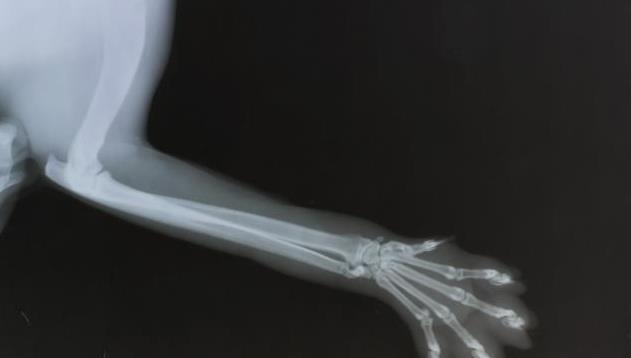

5个月大的肥大性骨营养不良的大丹犬尺骨X光片

X光线通常显示病变骨头的变化,例如与生长板平行线的外观,骨密度的变化以及生长板周围的钙化。